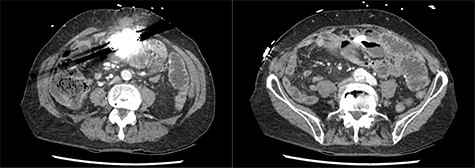

A presentation 6 weeks later was once again diagnosed as ASBO, with multiple segments of dilated small bowel with a transition point identified in the right iliac fossa on CT scan (Figs 1 and 2). On this occasion, operative management was required, with the AICD identified to the left of the umbilicis with extensive matted adhesions to small bowel encountered. Extensive adhesiolysis was undertaken at this area, with the defibrillator removed from the intra-abdominal cavity and repositioned in a subrectus pocket. Following the procedure, the AICD was reactivated and confirmed to be operating as expected. The patient responded well to operative management and began opening his bowels on the third day postoperatively. The patient tolerated a diet and was able to be discharged home. He was reviewed in the clinic 6 weeks after the laparotomy, and at this time it was found he had continued to open his bowels regularly and was undertaking his usual activities with nil issues. The patient had not had any further episodes or symptoms concerning for obstruction.

Coronal slices of computed tomography scan shown beam hardening artefact from intra-abdominal AICD, adjacent to distended loops of small bowel.